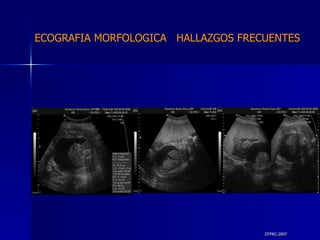

DTFRC-2007 ECOGRAFIA MORFOLOGICA  HALLAZGOS FRECUENTES   MATERIAL Y METODO ES UN ESTUDIO DESCRIPTIVO, RETROSPECTIVO  DE ESTUDIO ECOGRA FICOS REALIZADOS ENTRE MARZO 07 A MARZO 08 EQUIPO DE ALTA RESOLUCION   VOLUSON 730 PRO  MEDISON SA 8000 live MEDISON SA 8000SE CRITERIO DE INCLUSION:   POBLACION GENERAL    GESTACIONES  20 a 24 SEMANAS   UNIVERSO  N 211

DTFRC-2007 ECOGRAFIA MORFOLOGICA  HALLAZGOS FRECUENTES   Sistema Nervioso Central  8  Cardiovascular  0 Genitourinario  6 Musculos Esqueleticos  2 Gastrointestinales  2  Otros  12  Total  30   NUMEROS DE ANOMALIAS POR SISTEMA n N  211

DTFRC-2007 ECOGRAFIA MORFOLOGICA  HALLAZGOS FRECUENTES   SISTEMA NERVIOSO CENTRAL TOTAL  8  26 % 1 HIDROCEFALIA 2 VENTRICULO MEGALIA 4 QUISTE DE PLEXO COROIDEO 1 ANENCEFALIA

DTFRC-2007 ECOGRAFIA MORFOLOGICA  HALLAZGOS FRECUENTES   GENITOURINARIA DISPLASIA RENAL MULTIQUISTICA  3 HIDRONEFROSIS  2 QUISTE DE OVARIO FETAL  1 SISTEMA DIGESTIVO DILATACION INTESTINAL  2  SISTEMA ESQUELETICO   PIE BOT  2  20 % 6 % 6 %

DTFRC-2007 ECOGRAFIA MORFOLOGICA  HALLAZGOS FRECUENTES   OTROS HIGROMA QUISTICO  2 ENFERMEDAD ADENOMATOSA PULMONAR  1 ARTERIA UMBILICAL UNICA  2 HIDROPS FETAL NO INMUNE  1 QUISTE DE CORDON UMBILICAL  1 ALTERACION DE LIQUIDO ANMIOTICO  2 SINDROME TRAFUSIONAL FETO FETAL 1 LABIO LEPORINO  2 TOTAL  12  42 %